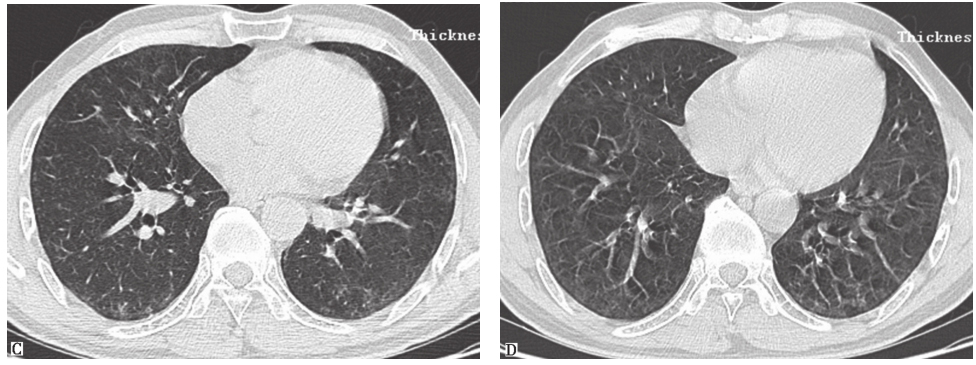

图12巨细胞间质性肺炎胸部影像学表现

男性患者,32岁,从事刀具磨制工作9年,经支气管肺活检病理证实为巨细胞间质性肺炎。CT示两肺散在磨玻璃影、小结节影、小片实变影、牵拉性支气管扩张

巨细胞间质性肺炎(giant cell interstitial pneumonia,GIP):是暴露于含有钴、碳化钨等硬金属及其化合物引起的少见职业相关性间质性肺疾病。其典型胸部CT表现为弥漫性磨玻璃影、小结节影、广泛网状影和牵拉性支气管扩张改变,以及大小不等的实变影(图12)。晚期患者可见肺部广泛的结构扭曲和蜂窝样改变。GIP最终诊断应该根据职业接触史、影像学特征和病理学等证据。本例患者从事钻孔工作8年,接触金属粉尘较多,有职业接触史,影像学特征也较符合GIP,但仍需获得病理学检查结果以明确诊断。